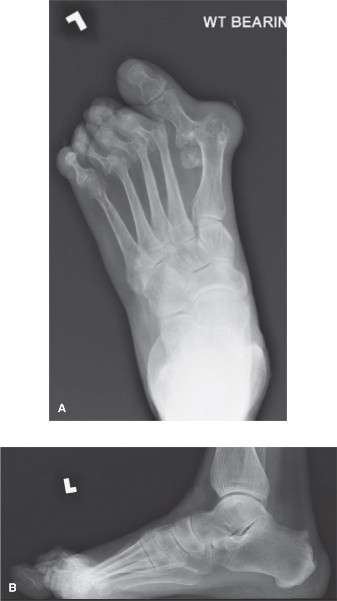

A 21-year-old, collegiate football player noted acute medial forefoot pain when he axially loaded a dorsiflex…